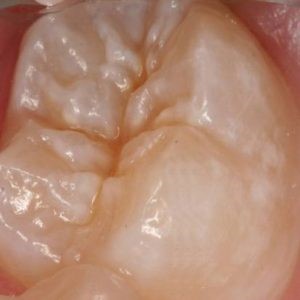

All posterior teeth have pot holes in them. But in medical terms they are not called pot holes. They are known as pit & fissures.

Brushing and flossing are the best ways to help prevent cavities, but it’s not always easy to clean every nook and cranny of your teeth – especially those back teeth you use to chew (called molars). Molars are rough, uneven and a favourite place for leftover food and cavity-causing bacteria to hide.

Cavities (dental caries) begin to develop within these pits and fissures. Sticky and retentive foods along with cavity causing bacteria and saliva lead to production of acids. These acids further break down the tooth, create holes and lead to cavity formation.